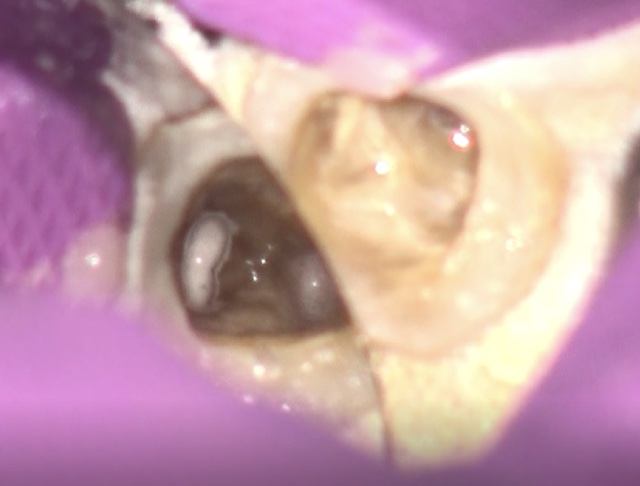

左上の前歯の見た目が気になることを主訴に来院されました。

虫歯を除去後、神経が露出しないように丁寧に削合しました。

仮歯に置き換え、見た目の確認をしてもらいました。

反対側に近い形となっており、元々の歯よりも大きいため、全体的に小さくしてほしいとの希望でした。

患者さんの希望を反映した補綴物が完成しました。

患者さんの希望の色味、形となりとても満足いただけました。